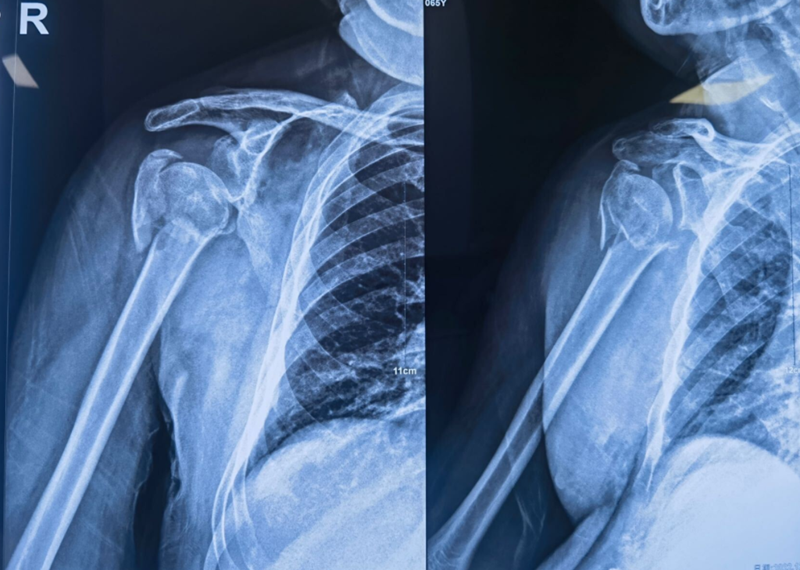

Xxx,男,65岁,右肱骨近端四部分骨折一周。

图16 术前X片

图19 术后X片